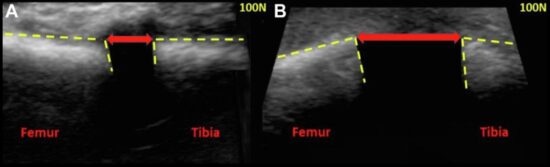

Figure. Ultrasound images of the medial compartment of the left knee taken at 20° of flexion with a portable ultrasound probe positioned perpendicular to the medial joint line over the medial collateral ligament. The medial tibiofemoral distance was calculated by measuring the distance between the articular margins (indicated by dashed yellow lines) of the medial femoral condyle and the medial tibial plateau. (A) Ultrasound image demonstrating medial tibiofemoral distance under 100 N of valgus force in an intact knee. (B) Ultrasound image demonstrating increased medial tibiofemoral distance under 100 N of valgus directed force after transection of the deep medial collateral ligament and posterior oblique ligament.

Results: Of the 8 cadaveric knees in this study, 3 were male and 5 were female; mean age was 58 ± 11 years (range 48–82 years). When measured using ultrasonography at 20° knee flexion with valgus load, the medial tibiofemoral distance significantly increased with increasing severity of medial knee injury (P values ranging from .049 to <.001). Optimal cutoff values for distinguishing between an intact knee and sMCL injury were 8.3 mm (area under the curve [AUC] = 0.98), between sMCL and dMCL injury 9.9 mm (AUC = 0.89), dMCL and POL 16.7 mm (AUC = 0.88), and POL and ACL 18.6 mm (AUC = 0.84). When the study authors compared combined intact and sMCL-transected stages with dMCL-transected stage, optimal cut-off point to differentiate stable from unstable injuries was equal to13.8 mm of medial tibiofemoral distance (AUC = 0.97; sensitivity = 100%; specificity = 94.1%).